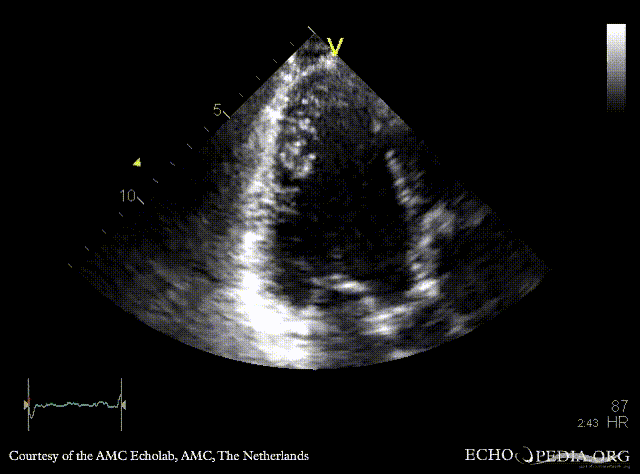

Tenting of mitral valve

Courtesy of: AMC Echolab, AMC, The Netherlands

PLAX: dilated left ventricle, poor function, tenting of mitral valve PLAX with Color Doppler: severe mitral valve regurgitation